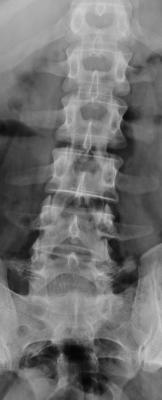

- forum_photo1.jpg (7.78 KiB) 9847 mal betrachtet

Offenbar handelt es sich bei der ersten Aufnahme um eine frontale Aufnahme, die eine Skoliose zeigt.

Dazu gibt es dann häufig in Kombination diese begleitende Skoliose.